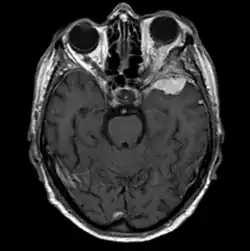

Sphenoid wing meningiomas are diagnosed by the combination of suggestive symptoms from the history and physical and neuroimaging by magnetic resonance imaging (MRI) or computer averaged tomography (CT). Tumors growing in the inner wing (clinoidal) most often cause direct damage to the optic nerve leading especially to a decrease in visual acuity, progressive loss of color vision, defects in the field of vision (especially cecocentral), and an afferent pupillary defect. If the tumor continues to grow and push on the optic nerve, all vision will be lost in that eye as the nerve atrophies. Proptosis, or anterior displacement of the eye, and palpebral swelling may also occur when the tumor impinges on the cavernous sinus by blocking venous return and leading to congestion. Damage to cranial nerves in the cavernous sinus leads to diplopia. Cranial nerve VI is often the first affected, leading to diplopia with lateral gaze. If cranial nerve V-1 is damaged, the patient will have pain and altered sensation over the front and top of the head. Horner's syndrome may occur if nearby sympathetic fibers are involved.

Tumors found in the external third of the sphenoid are of two types: en-plaque and globoid meningiomas. En plaque meningiomas characteristically lead to slowly increasing proptosis with the eye angled downward. Much of this is due to reactive orbital hyperostosis. With invasion of the tumor into the orbit, diplopia is common. Patients with globoid meningiomas often present only with signs of increased intracranial pressure. This leads to various other symptoms including headache and a swollen optic disc. The differential diagnosis for sphenoid wing meningioma includes other types of tumors such as optic nerve sheath meningioma, cranial osteosarcoma, metastases, and also sarcoidosis. Following the physical exam, the diagnosis is confirmed with neuro-imaging. Either a head CT or MRI with contrast such as gadolinium is useful, as meningiomas often show homogenous enhancement. Angiography looking for signs like stretched arteries may be used to supplement evaluation of vascular involvement and to determine whether embolization would be helpful if surgery is being considered.